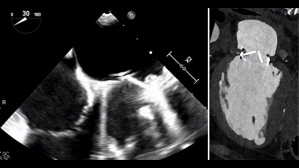

Ce patient de 86 ans est hospitalisé pour des lésions dermatologiques aspécifiques. Il présente plusieurs facteurs de risque cardiovasculaire : un tabagisme ancien, un diabète de type 2, de l’hypertension, une dyslipidémie et un surpoids. Il est également atteint d’une surdité non appareillée et d’une maladie aortique.